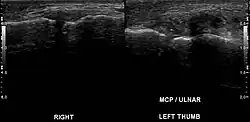

| Stener lesion on left thumb in ultrasound | |

A Stener lesion is a type of traumatic injury to the thumb. It occurs when the aponeurosis of the adductor pollicis muscle becomes interposed between the ruptured ulnar collateral ligament (UCL) of the thumb and its site of insertion at the base of the proximal phalanx. No longer in contact with its insertion site, the UCL cannot spontaneously heal.[1]